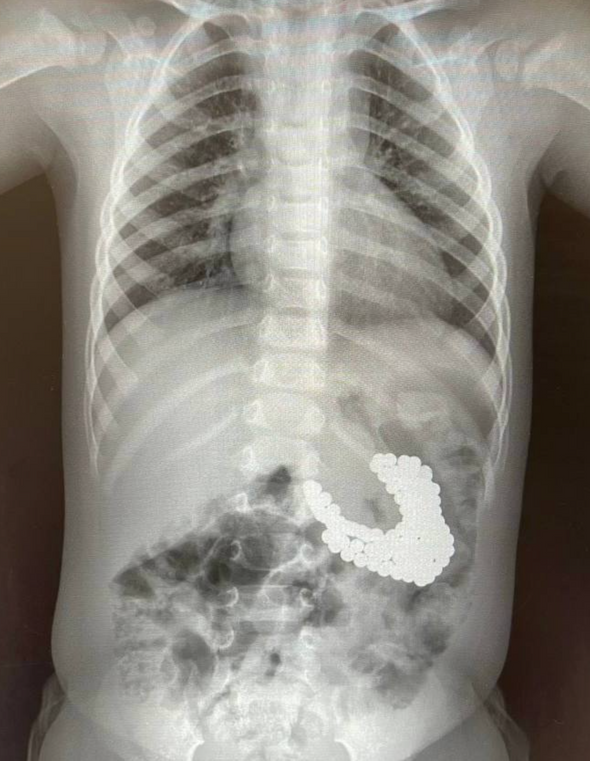

Врачи спасли полуторагодовалого ребенка, проглотившего 130 магнитных шариков и литиевую батарейку

Врачи клиники имени Рошаля извлекли из ЖКТ полуторагодовалого мальчика порядка 130 магнитных шариков и литиевую батарейку. Об этом сообщается на сайте минздрава Московской области.

В Детский клинический центр имени Рошаля поступил ребенок с подозрением на проглатывание инородных тел. Обследование выявило в желудке полуторагодовалого мальчика скопление большого количества магнитов и батарейку. Инородные тела необходимо было извлечь как можно быстрее, так как магниты и батарейки при соприкосновении со слизистой в организме очень быстро окисляются, что приводит к внутренним ожогам, перфорации внутренних органов, некрозу тканей и кровотечению.

Врачи рассказали, что с помощью специальных инструментов — эндоскопического «Сачка», зажима по типу «Аллигатор» и «Корзины Дормиа» провели гастроскопию. В ходе процедуры хирурги последовательно извлекли из желудка мальчика 130 магнитов и литиевую батарейку. Магниты сцепились друг с другом, что привело к повреждению слизистой оболочки и образованию язвы.

После эндоскопии врачей ждал неприятный сюрприз, так как на послеоперационном рентгене они обнаружили еще три магнита, которые невозможно было удалить с помощью эндоскопа. Ребенок, по всей видимости, глотал магниты в разное время, поэтому некоторые из них уже переместились в кишечник. Находясь там, они сцепились и притянули друг к другу желудок и кишечник. Извлечь опасные предметы можно было только хирургическим путем.

снимки: mz.mosreg.ru